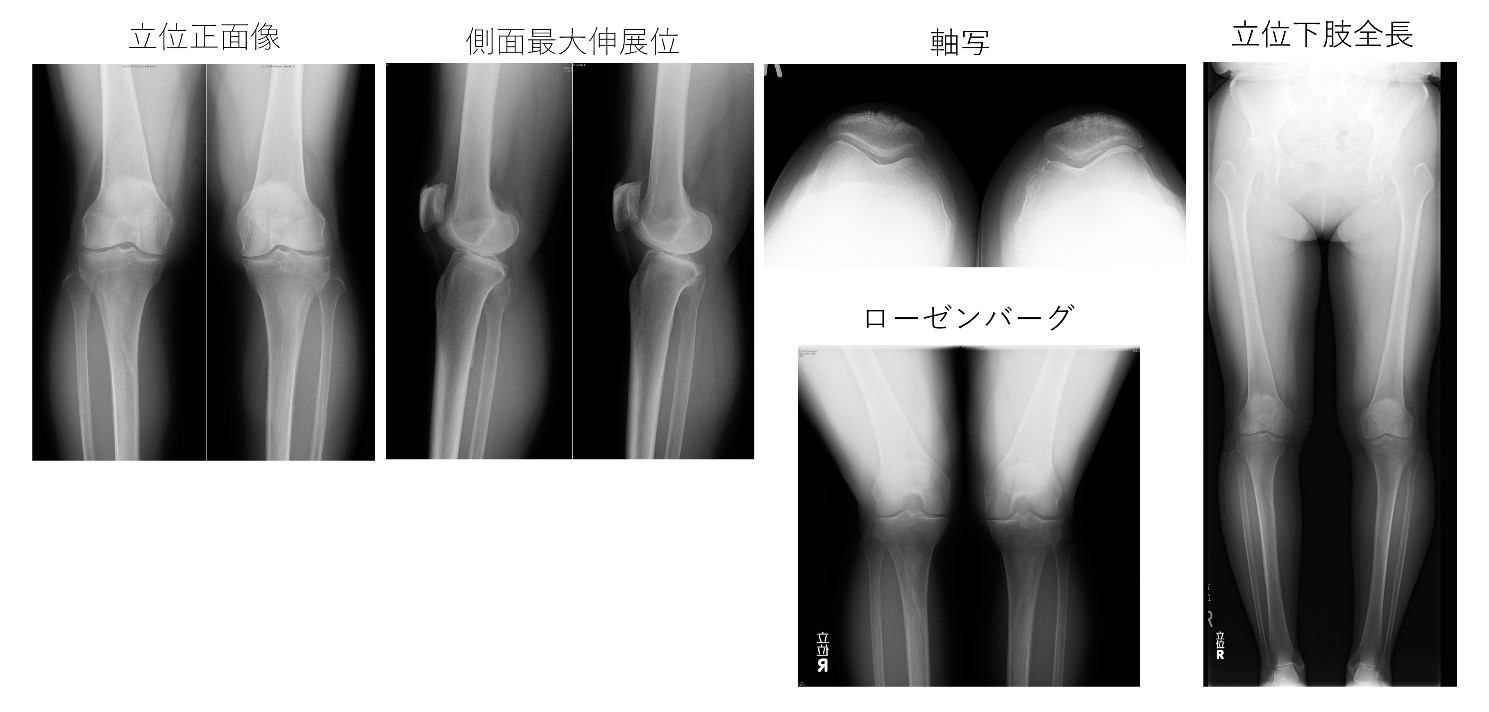

医師は通常、脚を検査し、歩き方を観察することで、内反膝の初期診断を下すことができます。また、骨の構造を詳しく調べるために、患部の脚のX 線検査を依頼する場合もあります。

医師が内反膝であることを確認した場合、角度計と呼ばれるツールを使用して、脚が外側に曲がる度合いを測定することもあります。